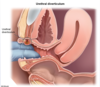

TVUS

s/f Placenta PREVIA, in which digital Cervical Exam is contraindicated since it enters endocervical canal. TVUS and speculum do NOT enter endocervical canal